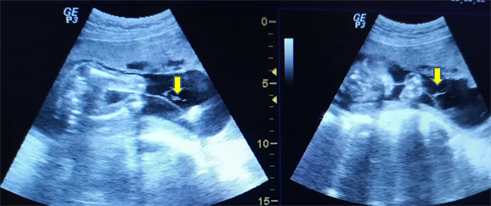

Discovery also in antenatal ultrasound of other malformative abnormalities of the bony skeleton such as exaggeration of the dorsal kyphosis with lumbar hyperlordosis, of the urogenital apparatus of the type major dilation of the pyelocalicielles cavities of the two kidneys without visualization of the bladder (Figure 2).

Figure 2. Obstetrical ultrasound showing the dilation of the bilateral renal cavities more marked on the right with the exaggeration of the dorsal kyphosis and the lumbar lordosis.